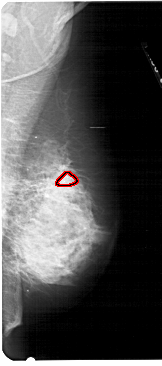

RIGHT_MLO LINES 5476 PIXELS_PER_LINE 2416 BITS_PER_PIXEL 12 RESOLUTION 43.5 OVERLAY

FILE: A_1222_1.RIGHT_MLO.OVERLAY

TOTAL_ABNORMALITIES 1

ABNORMALITY 1

LESION_TYPE MASS SHAPE ARCHITECTURAL_DISTORTION MARGINS SPICULATED

ASSESSMENT 5

SUBTLETY 5

PATHOLOGY MALIGNANT

TOTAL_OUTLINES 1

BOUNDARY